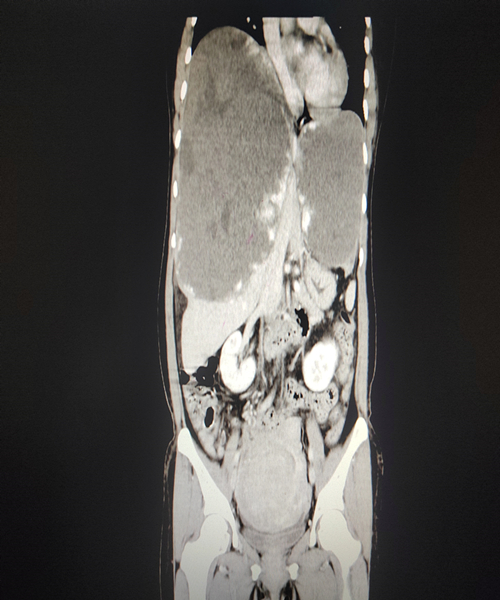

50岁的严女士近几年来觉得自己肚子“发福”了,一直未引起重视。十余天前,严女士自觉腹部“变硬”,于3月8日来到湘雅三医院肝肝胆胰外科I区门诊就诊。CT结果发现严女士所谓“发福”竟是肝脏上长了一个“篮球”大小的巨大肿瘤,占据大部分右侧肝脏,并引起左肝代偿性肥大,左肝也长了一个“小排球”大小肿瘤。罗宏武和患者及其家属反复沟通病情后,安排患者入住三十病区,完善相关手术前检查和准备工作,立即组织全科室疑难病例大讨论。经科室多位教授阅片分析后认为患者“肝巨大海绵状血管瘤”诊断明确,肿瘤累及肝脏S4、S5、S7、S8、S2段,肿瘤占据整个上腹腔,手术操作空间极其有限,肿瘤与肝门部重要血管紧密相连,肝切除范围大,预计出血量大,手术中和术后肝衰竭风险大,务必力求精准保留残余正常肝组织,最大程度保护患者肝功能。极大的手术风险,让手术这个抉择显得异常艰难。

但患者肝脏两处的巨大肿瘤,若还不进行处理,瘤体还会继续进行性增大,腹腔内压力将持续性增高,随时可能出现瘤体破裂大出血,犹如随时可能爆炸的“炸弹”,危及生命。汪长发副教授将手术预计方案和预备措施详细告知患者和家属,同时积极完善肝功能储备检查、肝脏三维重建精确计算残肝体积、评估肝周血管结构等充分的术前准备,同麻醉科团队、手术中心团队在术前充分讨论术中的血流动力学注意要点、自体血回输、手术器械准备等准备措施后,肝胆胰外科I科罗宏武主任、汪长发副主任医师、王晨阳总住院医师、唐达经治医师团队决定为患者实施手术。术中的实际情况比术前评估显得更为艰难,手术操作空间极度狭窄,严重影响手术进度,瘤体压迫导致无法完全暴露第一、第二肝门,在麻醉科、手术中心、输血科等多学科的共同努力下,历时7小时,顺利将肝脏两处瘤体完全精准切除(右肝血管瘤25cm*20cm*22cm,左肝血管瘤10cm*8cm*8cm),且完整保留了患者正常的S6、S3、S1段肝脏(精确保护残余正常肝组织流入流出道),麻醉复苏后安返病房。